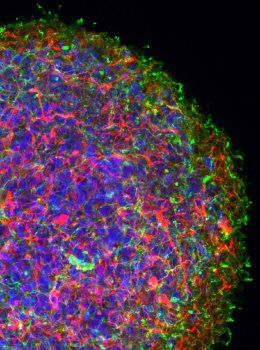

The Wonderful World of 3D+